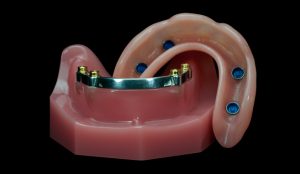

- All on 4

Dr. Paulo Maló, Portugal – All-on-4® treatment concept

Situation: Totally edentulous female patient in her early 50s, rehabilitated with upper and lower removable dentures over 15 years prior.

Solution: Fixed implant-supported bimaxillary rehabilitation using the All-on-4® treatment concept. The NobelGuide protocol (flapless) is followed in the maxilla and the conventional flap technique with the All-on-4® Guide is followed in the mandible. As a final prosthesis, fixed precision-milled NobelProcera Implant Bridges were chosen for both the maxilla and the mandible.